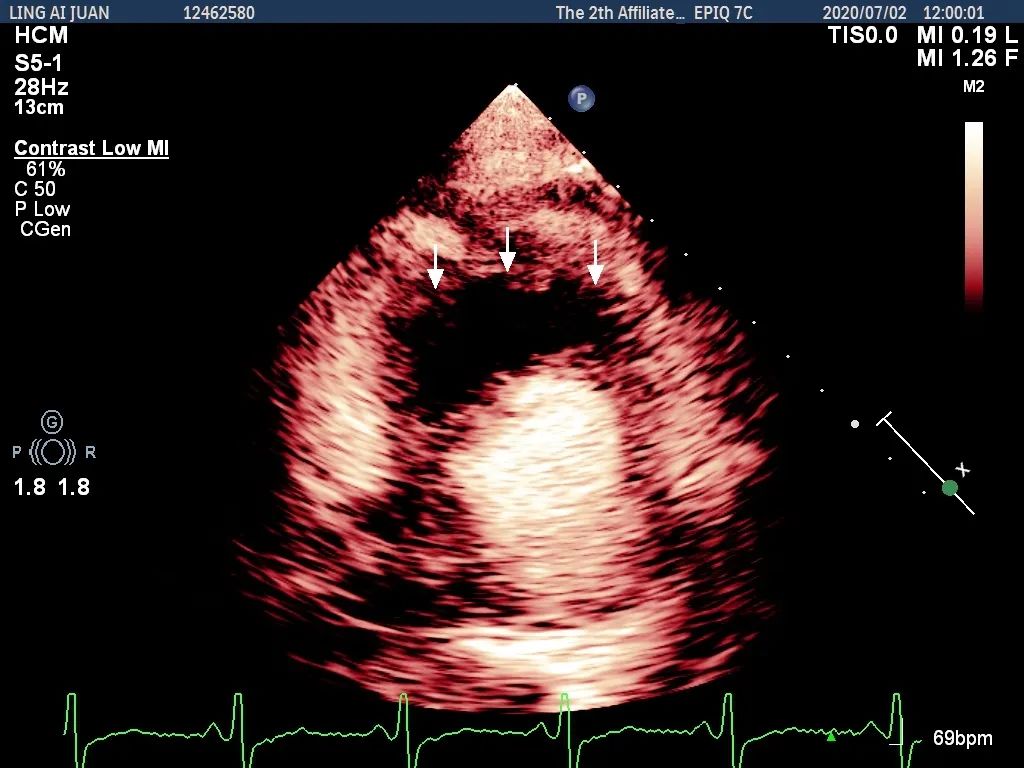

术前心肌超声造影示肥厚室间隔内丰富的穿隔支

Liwen术式成功消融术后心肌造影示“黑洞”效应